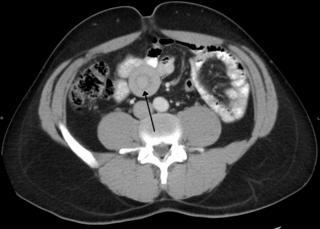

Инвагина́ция кише́чника — выделяемый в отдельную нозоформу вид непроходимости кишечника, причиной которого является внедрение одной части кишечника в просвет другой.

Перекру́т яи́чка — патологическое состояние, заключающееся в повороте яичка относительно его нормального положения, что приводит к сдавливанию сосудов и нервов, проходящих в составе семенного канатика. Без экстренного лечения данная патология приводит к развитию ишемических изменений в яичке, вплоть до необратимых нарушений функций железы и её омертвления (некроза).